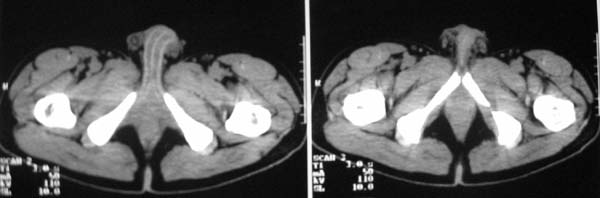

以下是引用zjzjr在2007-9-27 22:20:00的发言:[br]肠腔受推移,未见明显扩张及液平,所以考虑是肠外病灶, 间叶源性肿瘤?脂肪瘤?建议增强。

以下是引用guzhongliangddd在2007-9-27 23:21:00的发言:[br][br]与肠内高密度相同,病灶应该没有钙化,我认为首先考虑是间叶组织的良性肿瘤。建议楼主做后重建观察。中线区域大血管旁未见确切增大淋巴结。病灶对肠道只是推移关系。

以下是引用余辉在2007-9-27 22:24:00的发言:[br]暂考虑肠道间质来源肿瘤如小肠平滑肌肉瘤/瘤可能,应该增强